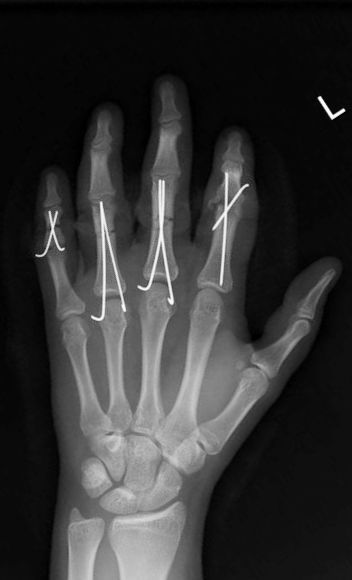

Hsu LP, Schwartz EG, Kalainov DM, Chen F, Makowiec RL. Complications of K-wire fixation in procedures involving the hand and wrist. J Hand Surg Am 2011;36(4):610-6.

Subramanian P, Kantharuban S, Shilston S, Pearce OJ. Complications of Kirschner-wire fixation in distal radius fractures. Tech Hand Up Extrem Surg 2012;16(3):120-3.

Gillis JA, Lalonde J, Alagar D, Azzi A, Lalonde DH. K-wire fixation of closed hand fractures outside the main operating room does not increase infections. Plast Reconstr Surg Glob Open 2022;10(11):e4679.

Abul A, Karam M, Al-Shammari S, Giannoudis P, Pandit H, Nisar S. Peri-operative antibiotic prophylaxis in K-wire fixation: a systematic review and meta-analysis. Indian J Orthop 2023;57(7):1000-7.

Ridley TJ, Freking W, Erickson LO, Ward CM. Incidence of treatment for infection of buried versus exposed Kirschner wires in phalangeal, metacarpal, and distal radial fractures. J Hand Surg Am 2017;42(7):525-31.